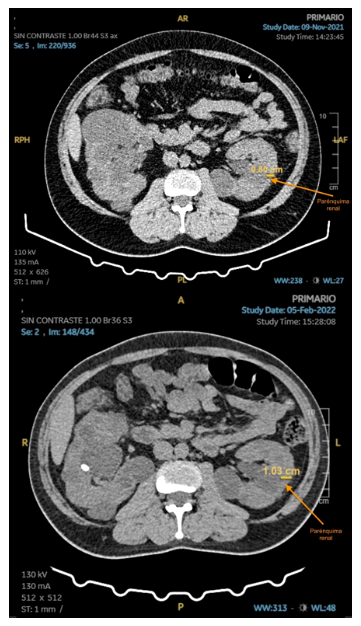

El volumen de los riñones fue medido por TC, tanto al inicio como en el control a las 12 semanas (Tabla 2) y el examen fue realizado sin contraste, las imágenes por TC tienen una precisión y coeficiente de confiabilidad similares a los de la RM 6 y son más accesibles para el paciente. Para el último control, se indicó una RM renal sin contraste. Al comparar las imágenes iniciales con el control de 12 semanas, se aprecia reducción del volumen de ambos riñones, así como el incremento del parénquima renal medido a nivel del hilio renal (Figuras 1 y 2). No se pudo contar con los formatos digitales de la RM para realizar la medición del parénquima en la semana 64.

Figura 1. UROTEM de riñón izquierdo donde se aprecia parénquima a nivel de hilio renal, basal (imagen superior) y al finalizar la semana 11 de VLCKD (imagen inferior).